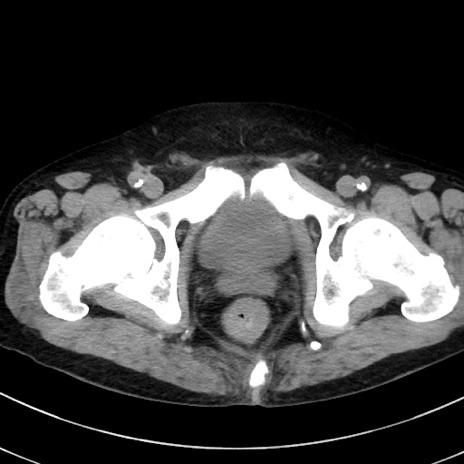

症例38(横断像)

【症例】70歳代 男性

【主訴】腹痛・嘔吐

【現病歴】昨晩より、嘔吐・腹痛あり。今朝になっても嘔吐あり。来院。

【既往歴】心臓バイパス手術、開腹胆摘、腸閉塞

【身体所見】BP 107/71mmHg、HR 116/min、腹部:平坦、軟、下腹部に軽度圧痛あり。反跳痛なし。

【データ】WBC 15100、CRP 0.32